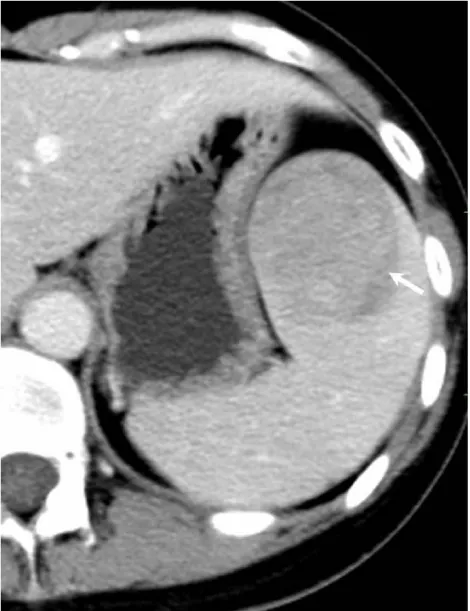

Solitary well-circumscribed masses were detected in all the five patients by ultrasound. One mass was of hypoecho, while the remaining masses were of hyperecho with posterior enhancement (Figure 1A). The maximum diameter ranged from 3.0 cm to 9.0 cm. At CT scanning, two masses appeared as hypodense (Figure 1B) and one was isodense (Figure 2A) to the normal spleenic parenchyma. In the two patients who received MR imaging, masses were isointensity at T1 weighted images (Figure 3A) and hypointensity with scattered sign void spots at T2 weighted images (Figure 3B). After intravenous injection of the contrast materials, all the five masses presented circle enhancement at arterial phase (Figure 3C and Figure 4A), while peripheral enhanced node was noted in one mass (Figure 2B). The circle enhancement persisted and radical line enhancement were observed at portal vein phase in 3 cases (Figure 1C) and progressive filling in was seen in two cases (Figure 2C). At delay phase of MR imaging, one lesion showed obvious enhancement with stellate low signal scar in the center comparing with surrounding splenic parenchyma (Figure 3D), while the other demonstrated central and circle enhancement to form a spoke-like appearance (Figure 4B). At delay enhanced CT scanning, two masses were isoattenuation to the surrounding splenic parenchyma (Figure 2D) and one lesion kept as hypoattenuation but with radial enhanced lines and enhanced circle to form a spoke-like appearance.

It usually affects middle-aged adults [6] and it is commonly found incidentally on radiographic imaging, or during operation for an unrelated condition. In present series, the patients are middle-aged adults without any related symptoms and the lesions were detected incidentally at routine ultrasound of health examinations. On ultrasound, manifestations of SANTs are vary widely from heterogeneous echo-texture with hyperechogenic, hypoechogenic, or isoechogenic appearing lesions, which are unspecific [7,8]. CT and MRI can show some characteristic features of SANTs, which include a solitary well demarcated mass with early peripheral enhancemant with radiating lines and progressive enhancement at the delay phase, and hypointens at T2 weighted MR images [2,3,5,9-13]. These features reflect the underlying pathological changes of scattered angiomatoid nodules separated and surrounded by sclerotic fibrotic stroma [10]. In present series, we also observed these characteristic features with well correlation to pathological findings. Circle and spoke-like enhancement can be contributed to fibrotic stroma surrounding and separating the angiomatoid nodules. The sclerotic fibrotic stroma may also result in isodense on CT, isointensity on T1 weighted images and hypointensity on T2 weighted images of MR imaging. The signal void spots at T2 weighted MR images have not been described at other literatures and may be contributed to hemosiderin deposition due to magnetic susceptibilty artifact.